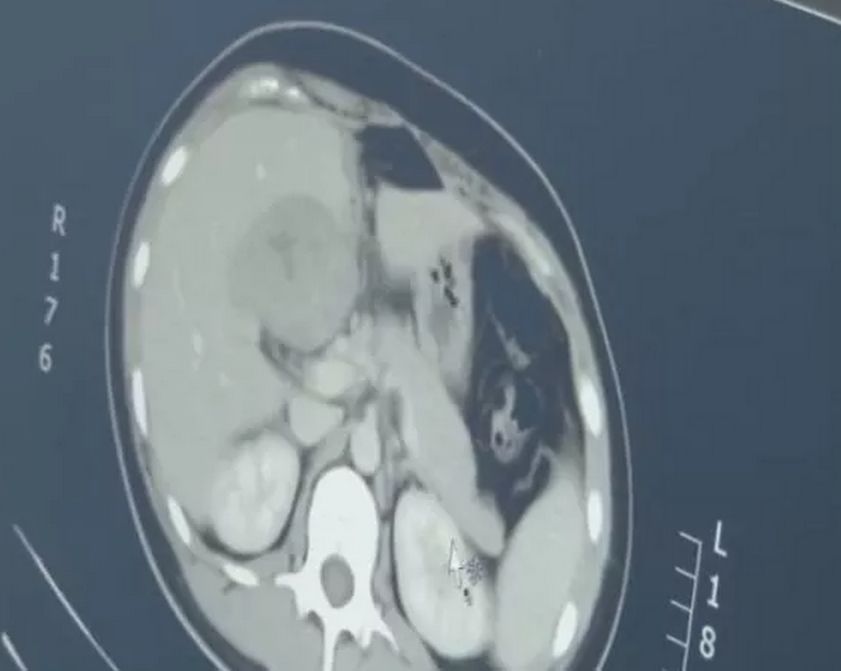

通過B超檢查發(fā)現(xiàn)胚胎未按照正常時間發(fā)育,如未按時出現(xiàn)胚芽、胎心等,可能是空孕囊的表現(xiàn)。

10、羊水過少或無羊水

羊水是胎兒生長的重要環(huán)境,如B超檢查發(fā)現(xiàn)羊水過少或無羊水,可能是空孕囊的征兆。